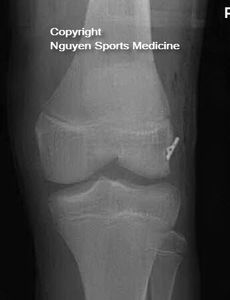

- MPFL reconstruction